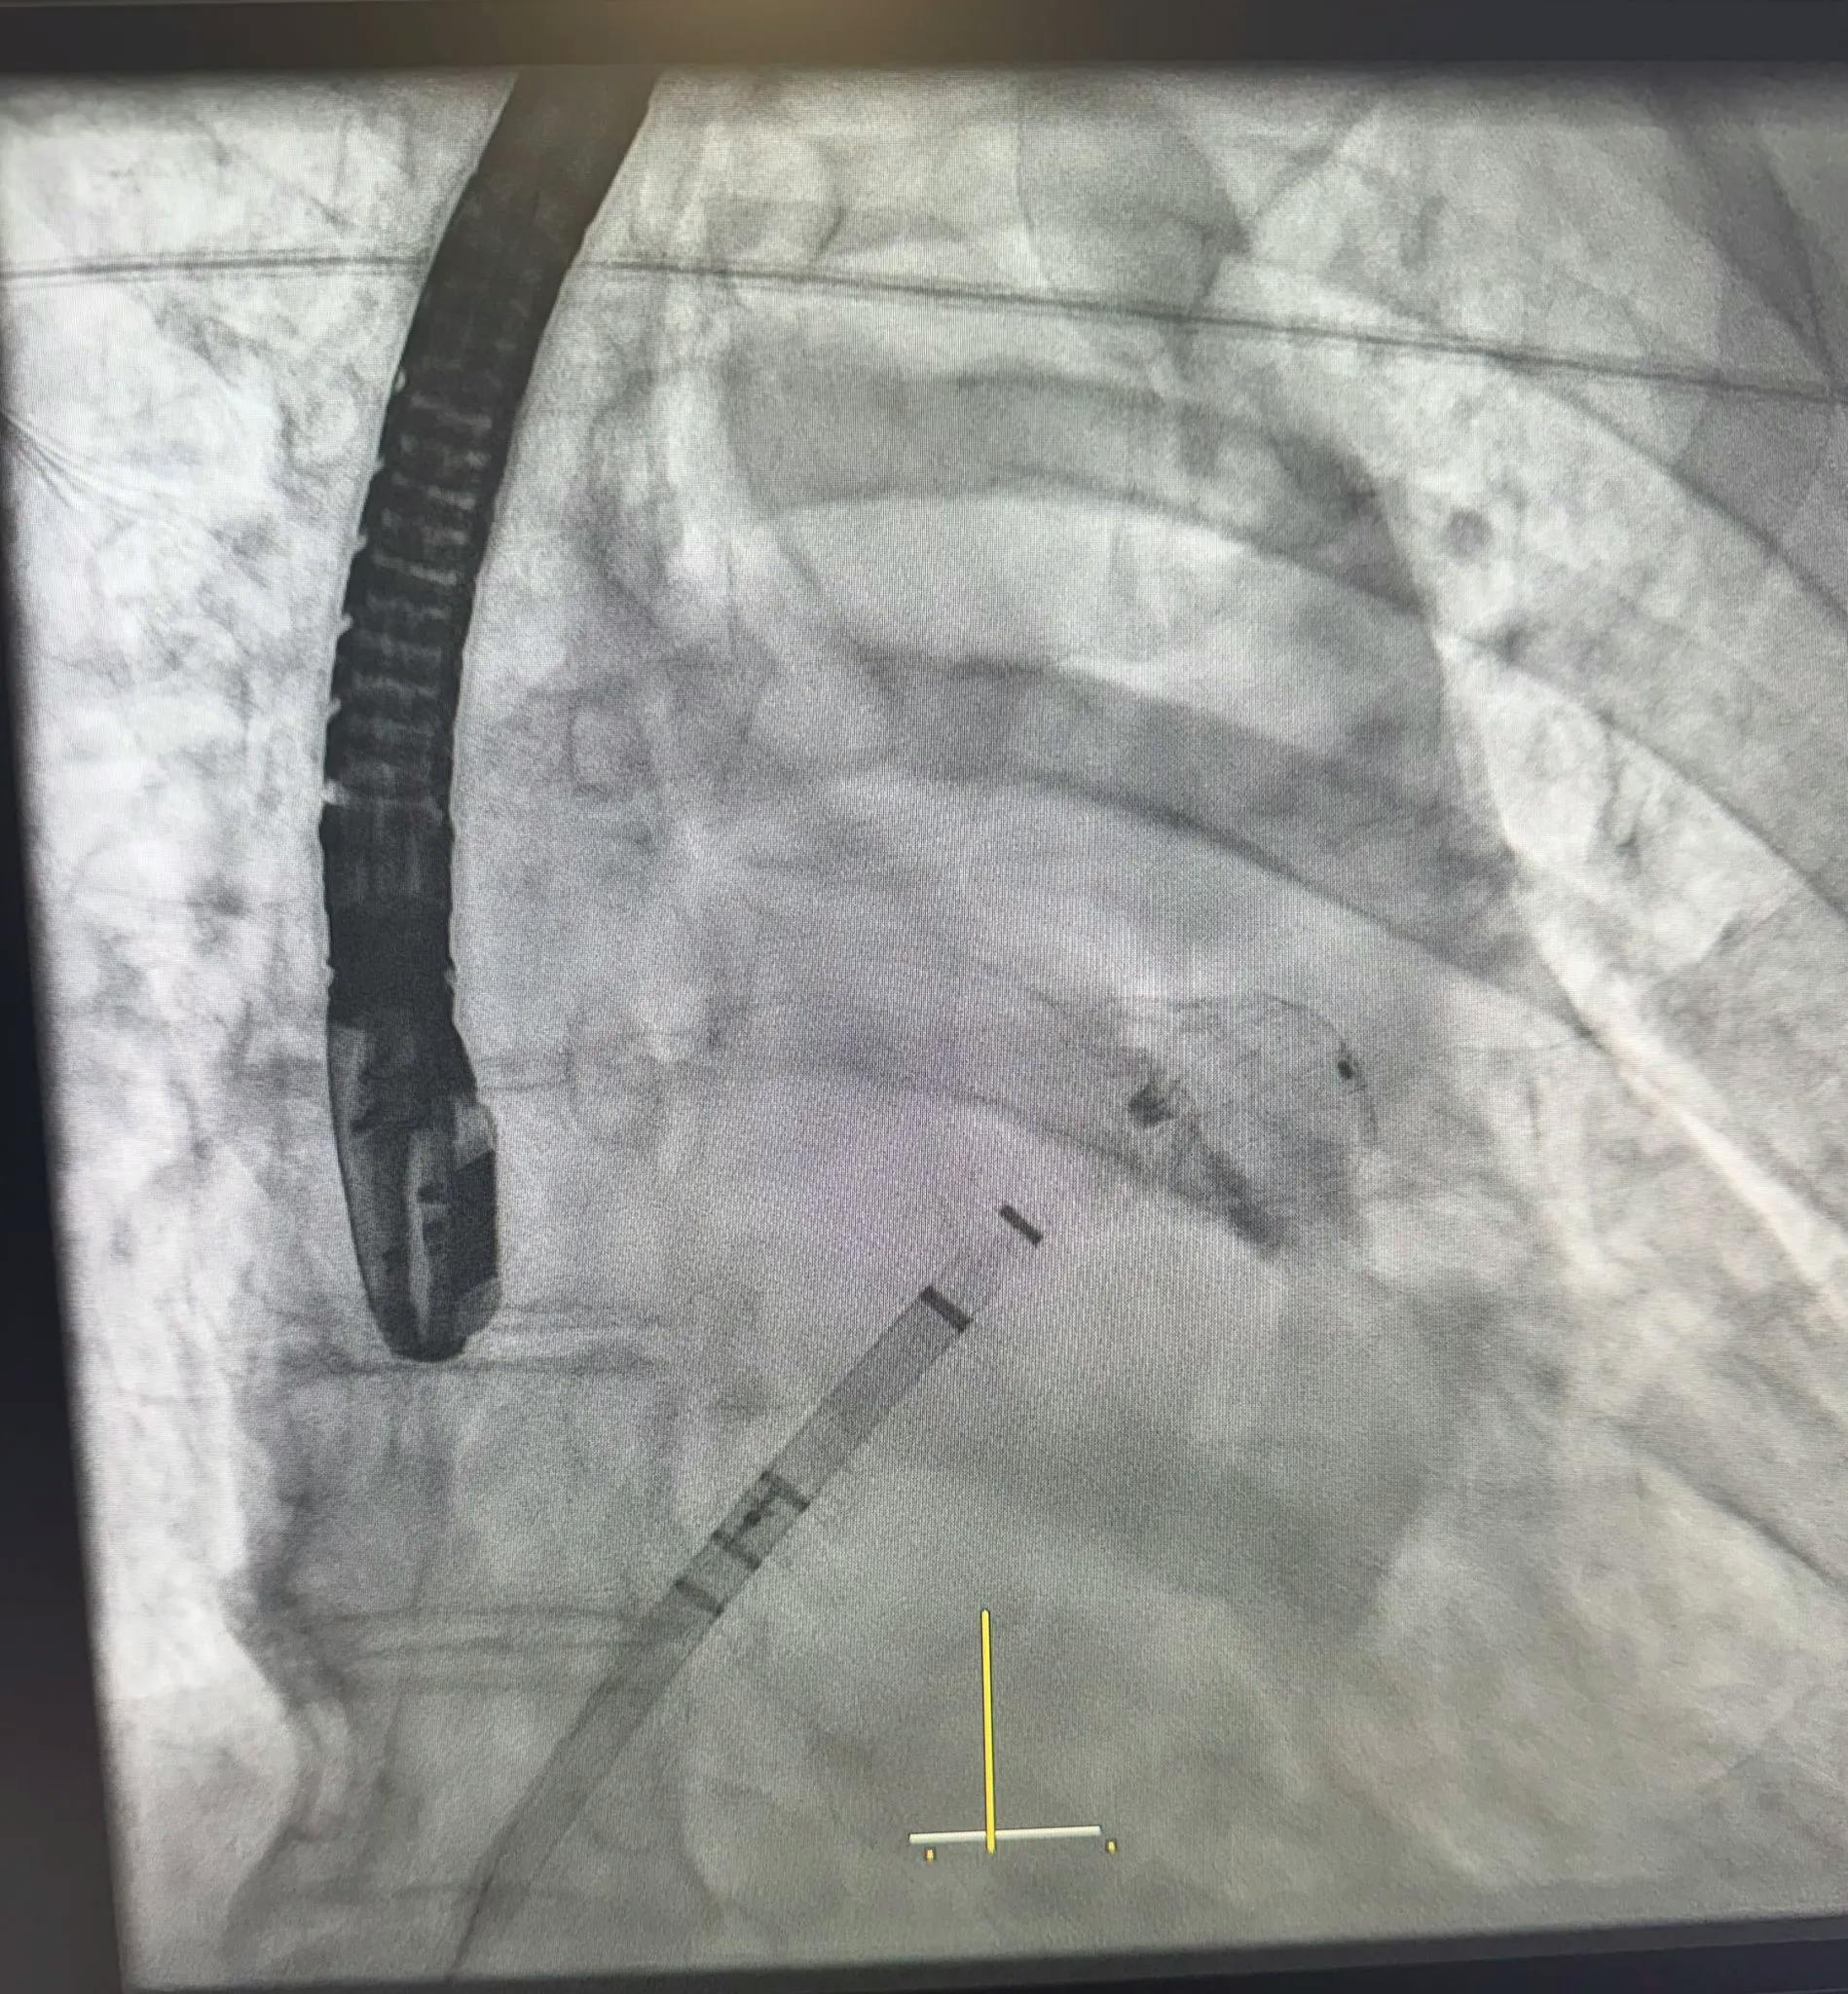

Procedura de implantare a dispozitivului Watchman

Implantarea a fost realizată de Dr. Nicolae Cârstea, alături de Dr. Dan Deleanu, cu ghidaj ecocardiografic transesofagian în timp real asigurat de Dr. Silvia Deaconu.

Intervenția s-a desfășurat microinvaziv, prin abord venos femural, fără chirurgie pe cord deschis, cu poziționarea optimă a dispozitivului și excluderea completă a auriculului stâng.

Procedura a avut loc sub supervizarea unui proctor internațional cu vastă experiență, Dr. Apostolos Tzikas, respectând cele mai înalte standarde de siguranță.